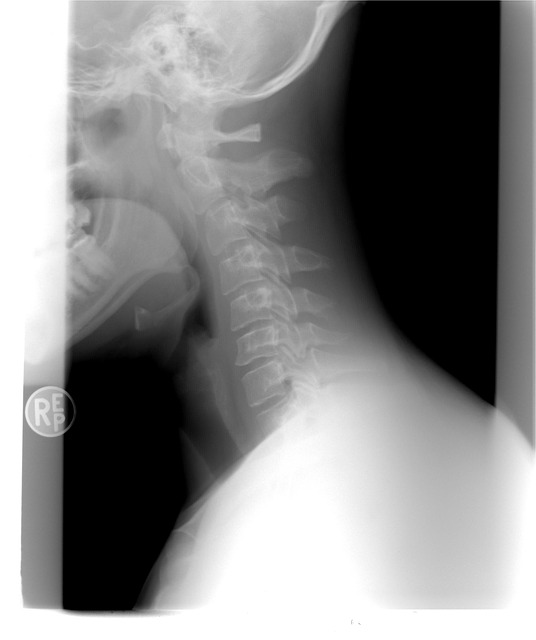

안녕하세요 ~ 오늘은 우리의 신체기관 중 갑상선과 관련된 증상과 치료 방법을 소개해 보는 시간입니다. 갑상선이란 우리 목에 위치해 있고, 신진대사에 필요한 갑상선 호르몬을 분비하는 내분비기관을 일컫습니다.

각종 대사에 필요한 호르몬이기 때문에 갑상선은 매우 중요합니다. 평소에는 놓치기 쉽지만 갑상선 이상 증상이 발생할 경우 일상생활에 불편함을 느끼고 종양이 발생할 수 있습니다. 전 세계적으로 약 5% 정도 가질 수 있다고 하니, 나는 그럴 일 없을 거야라고만 생각할 부분은 아닐 것입니다.